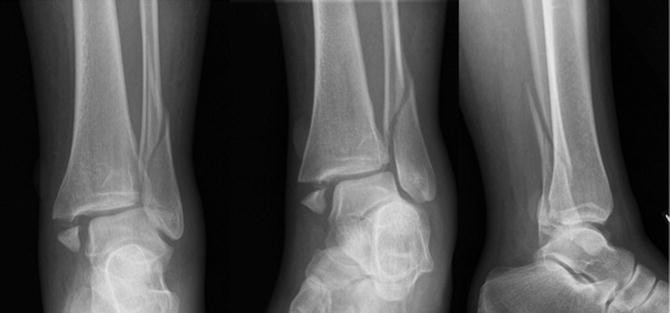

A tibial plafond or tibial plateau fracture is a fracture that occurs at the junction of the tibia and fibula bones in the knee. In this blog, we will discuss what tibial plafond is, its symptoms, and treatment.

The tibial plafond is the name given to the junction between the tibia and the fibula. It is usually seen when the tibia is fractured.

A tibial plafond fracture usually occurs when the tibia, the larger of the two bones in the knee, moves upward and forward and compresses the smaller bone, the fibula. This causes a small crack in the tibial surface of the fibula.